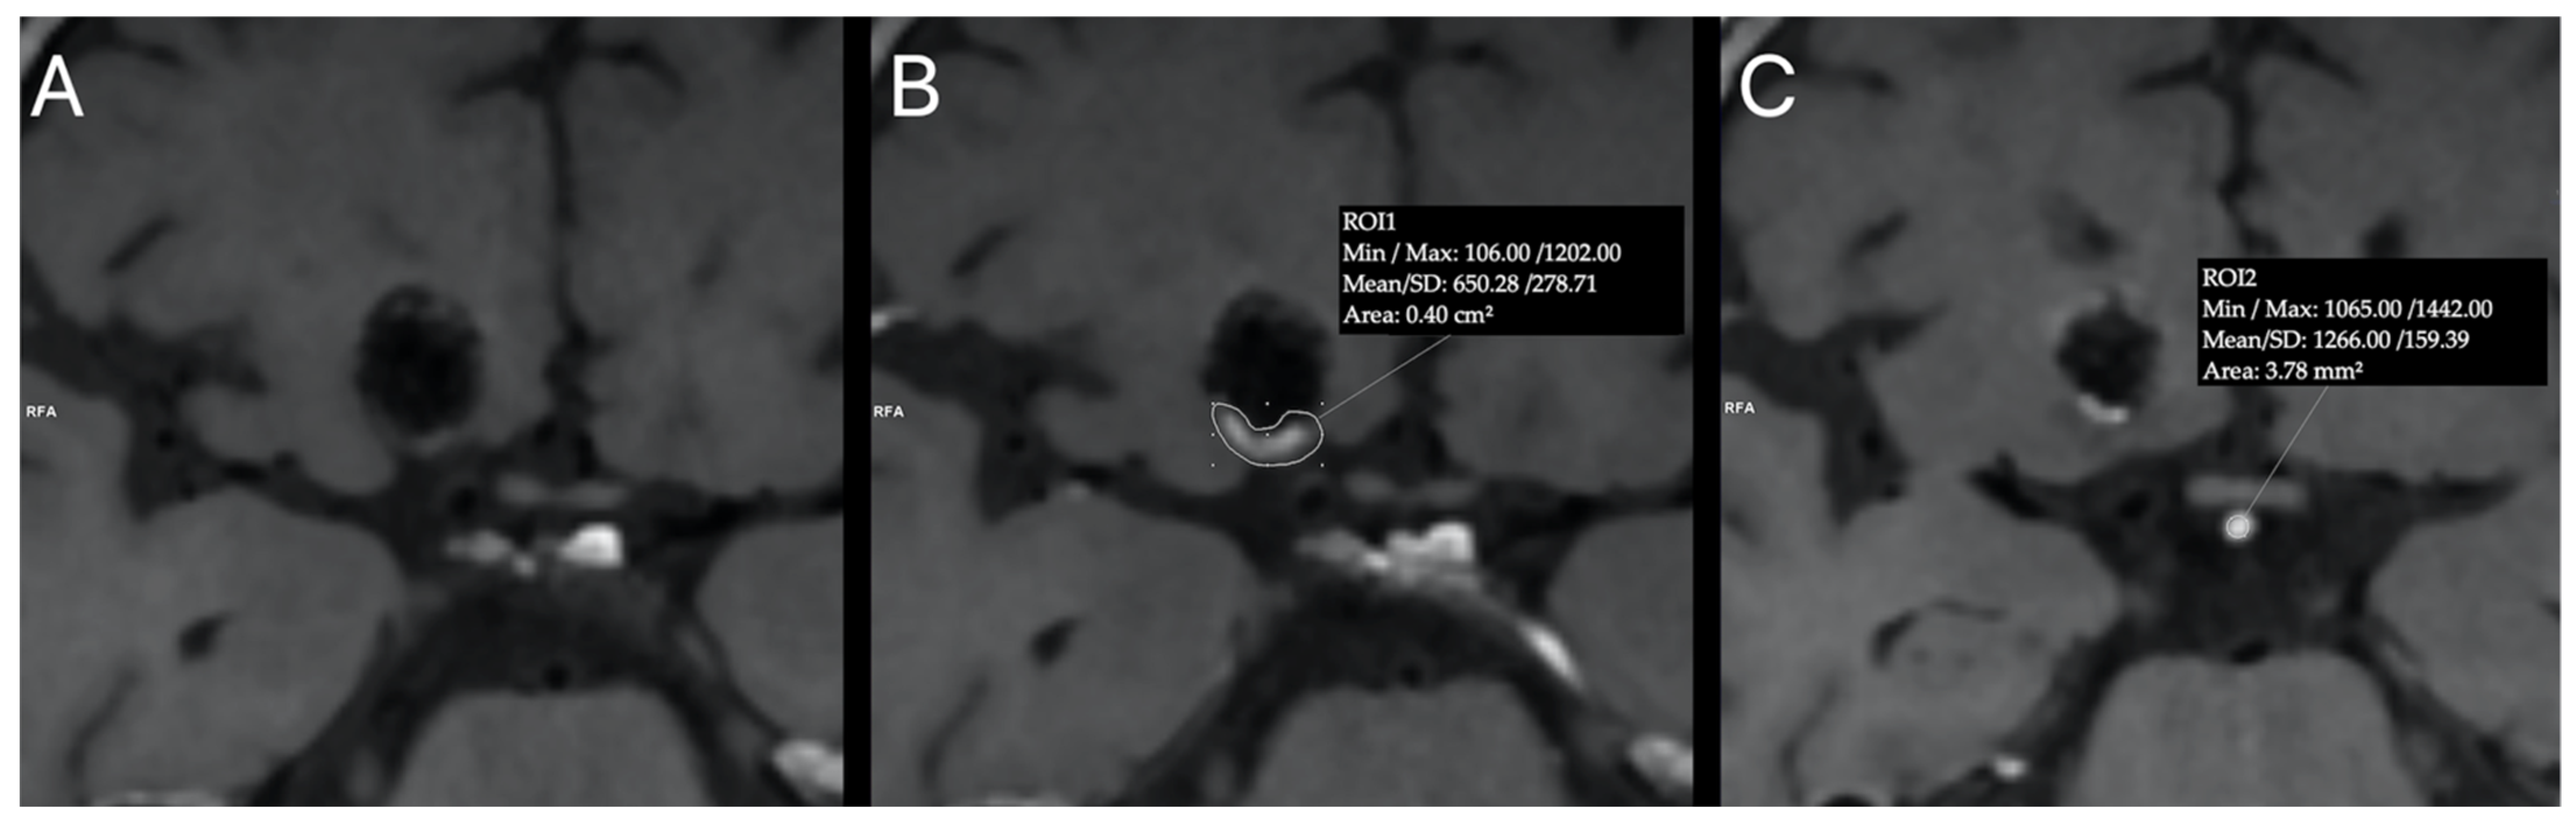

- Roa, J.A.; Zanaty, M.; Osorno-Cruz, C.; Ishii, D.; Bathla, G.; Ortega-Gutierrez, S.; Hasan, D.M.; Samaniego, E.A. Objective quantification of contrast enhancement of unruptured intracranial aneurysms: A high-resolution vessel wall imaging validation study. J. Neurosurg. 2020, 134, 862–869. [Google Scholar] [CrossRef]

- Omodaka, S.; Endo, H.; Niizuma, K.; Fujimura, M.; Inoue, T.; Sato, K.; Sugiyama, S.-I.; Tominaga, T. Quantitative Assessment of Circumferential Enhancement along the Wall of Cerebral Aneurysms Using MR Imaging. Am. J. Neuroradiol. 2016, 37, 1262–1266. [Google Scholar] [CrossRef] [Green Version]

- Zwarzany, Ł.; Tyburski, E.; Poncyljusz, W. High-Resolution Vessel Wall Magnetic Resonance Imaging of Small Unruptured Intracranial Aneurysms. J. Clin. Med. 2021, 10, 225. [Google Scholar] [CrossRef]